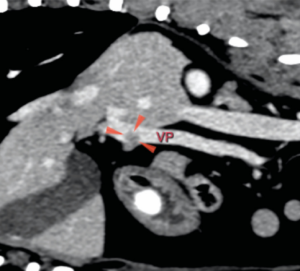

La ecografía abdominal reveló una lesión en el parénquima del cuerpo pancreático con posible invasión vascular a la vena porta. Una TC abdominal con contraste evidenció la lesión asociada al cuerpo del páncreas, con invasión de la vena porta (imágenes 1A y 1B), junto con la presencia incidental de un cuerpo extraño gástrico y signos de enfermedad degenerativa torácica y lumbosacra. Se realizó la extracción endoscópica del cuerpo extraño mediante gastroscopia durante el procedimiento anestésico.

Se realizó una laparotomía exploratoria por línea media ventral y se observó un nódulo en el cuerpo del páncreas con invasión de un trombo tumoral en la vena porta y otro nódulo de menor tamaño en el lóbulo izquierdo (imágenes 2A y 2B).